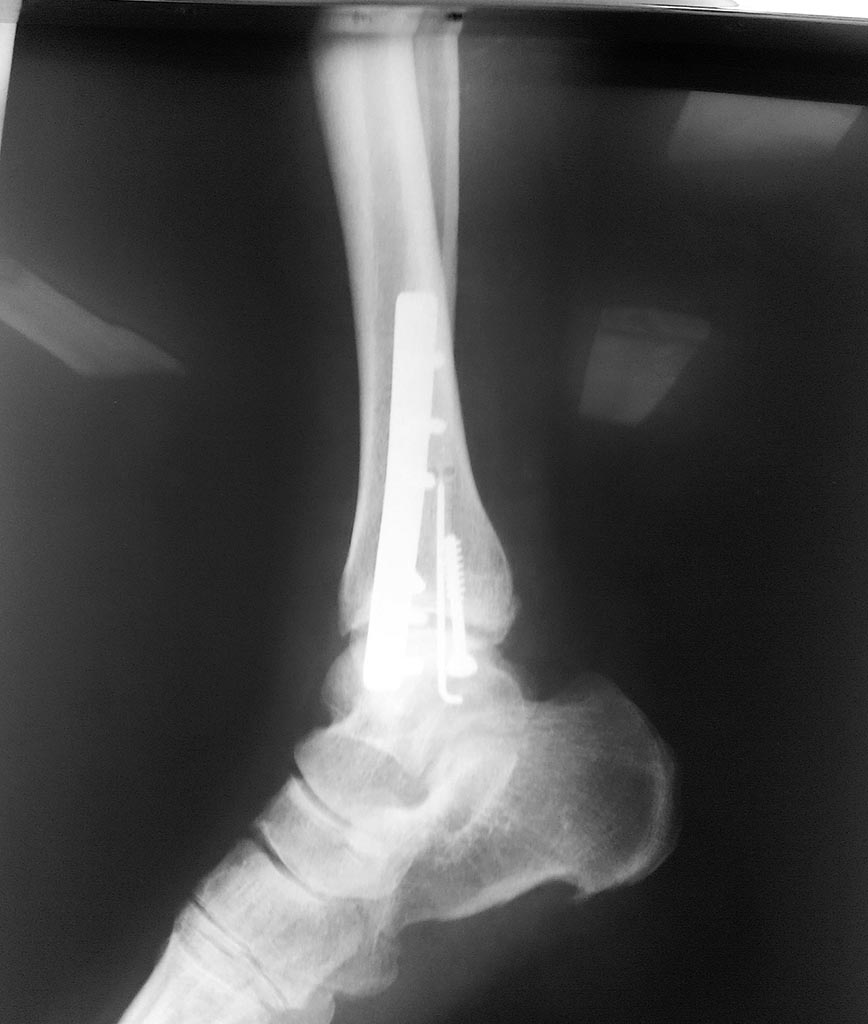

Здравствуйте. Женщина 56 лет, чрезсиндесмозный 3х-недельный перелом лодыжек.

Мнения коллег о сохраняющимся подвывихе стопы разошлись. Смущает визуальное расширение медиального лодыжечного пространства, хотя вся суставная щель примерно одинакова и равна 4-5 мм.

Добавлены снимки

Для оценки желательно сделать сравнительные снимки обоих голеностопных суставов в проекции мортис, без них сложно дать ответ. Не совсем понятно полностью ли восстановлена длина латеральной лодыжки.